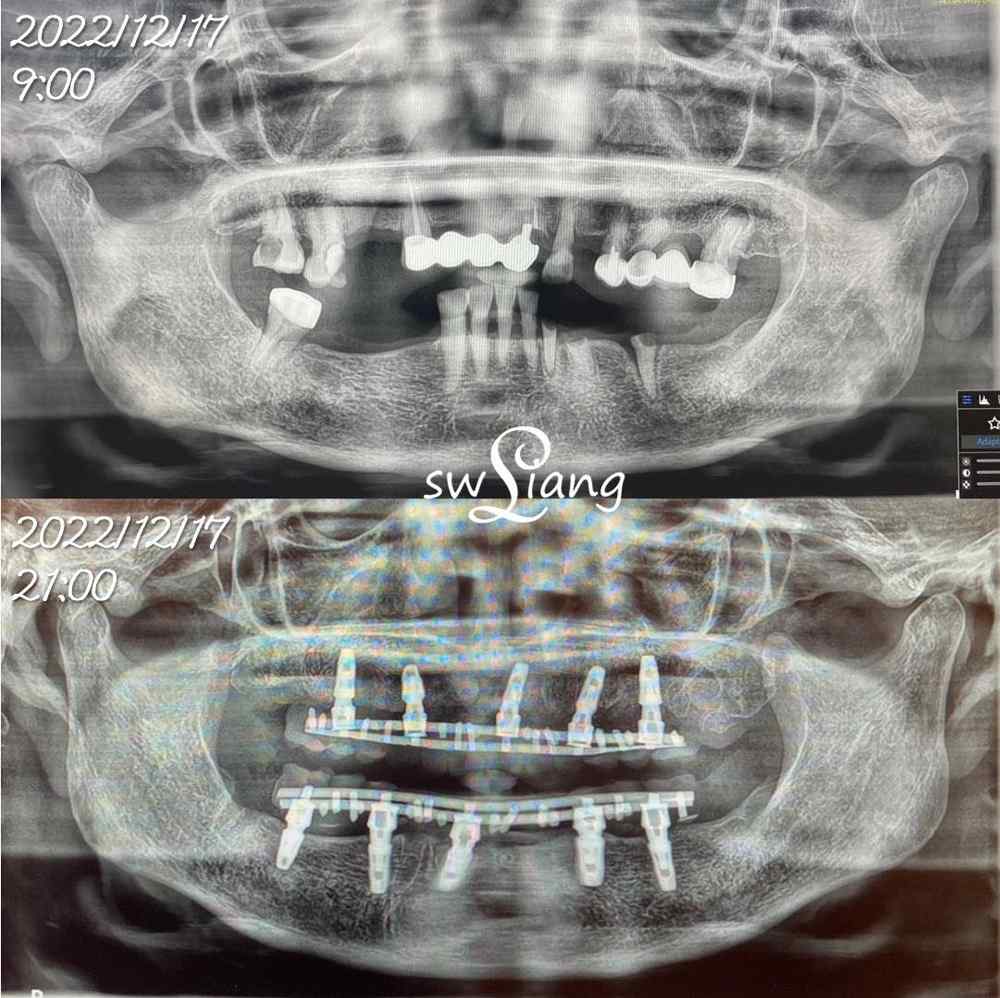

12個小時

改變一位77歲的長輩

完成上下顎的固定假牙

全口重建(ALL ON 4/6) 案例